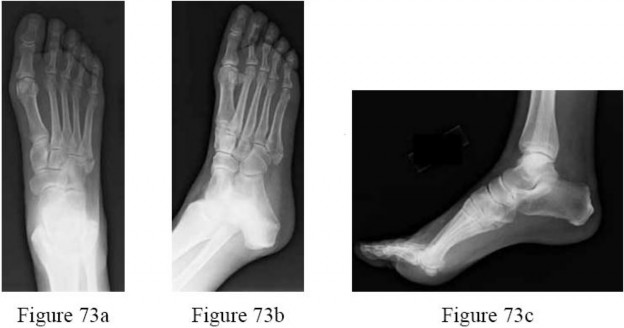

-are the radiographs of a 57-year-old woman who twisted her ankle stepping off a curb and now has lateral foot pain. Examination reveals intact skin and point tenderness over the base of the fifth metatarsal. What is the most appropriate treatment?